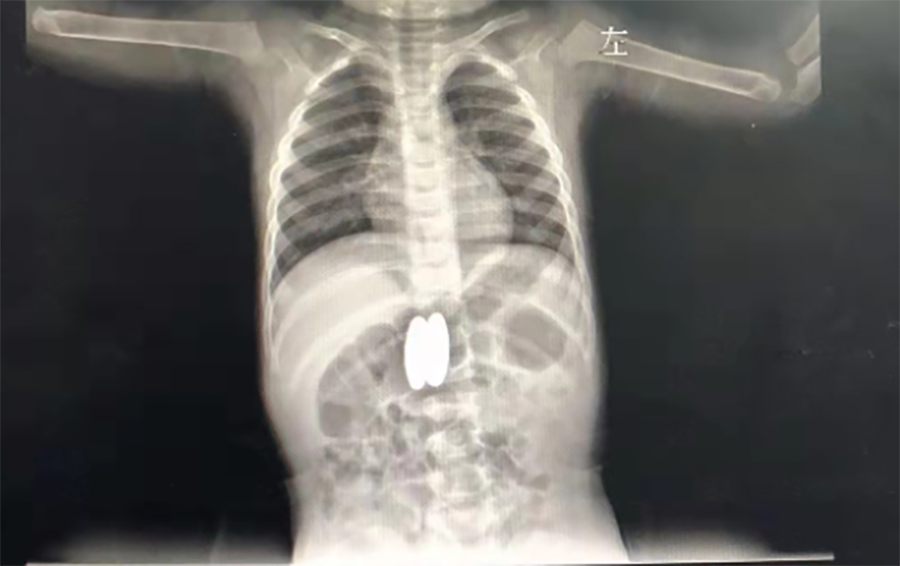

正月初八,2岁的壮壮(化名)感冒加重了,不断咳嗽,家人带他到当地医院就诊。在拍肺CT时,医生发现他的胃、肠里竟然有两个异物,而且两处异物竟吸在一起了。

▲当地医院CT

家长回想起春节前大宝的4个磁力球少了2个,怎么找都没找到,看来是被二宝误吞了。当地医生担心壮壮胃肠穿孔,建议他们马上带壮壮到a片网站 就诊。在内镜中心,副主任边鹏经内镜检查,发现壮壮吞下的磁力球直径有2cm,呈椭圆形,分别在胃体后壁、十二指肠球部。考虑到误吞异物时间较长,两球相吸处很可能已经穿孔,内镜中心同外科会诊,迅速研究解决方案。边鹏说,一是手术治疗,但十二指肠周围有胆管、大血管等,周围组织特别敏感,一旦出问题,危险性极大;二是保守治疗,在生命体征平稳的情况下,暂时观察,待胃、肠穿孔形成窦道,就可以不用手术,在内镜下把异物取出来了。经沟通,家长选择保守治疗,择日再来取出异物。